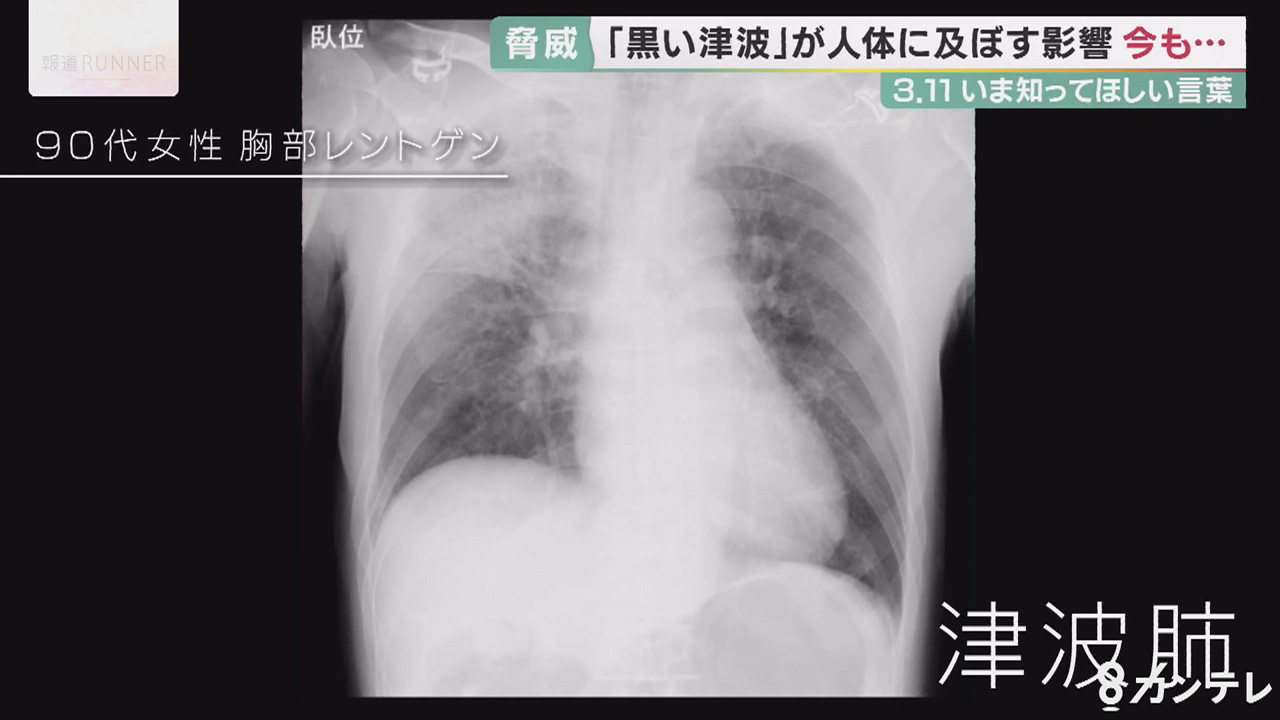

「黒い津波」に流された90代の女性のレントゲン写真。

広範囲に白い影があり、「津波肺」と呼ばれる重い肺炎症状がみられます。

海水とともに汚れた泥などを飲み込んだことが原因とみられ、女性は搬送から4日後に死亡しました。